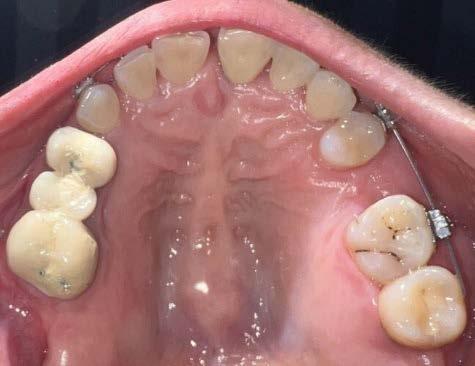

Introducción: La maloclusión clase II provoca proporciones irregulares en el perfil facial. Puede deberse a un maxilar adelantado y a incisivos superiores proinclinados y protruidos. Esta condición puede corregirse mediante el uso de aparatos ortopédicos en pacientes en crecimiento.

Objetivos: Conseguir clase I canina, controlar el crecimiento vertical, disminuir la convexidad esqueletal, reducir la sobremordida horizontal y mejorar el perfil facial. Caso clínico: Paciente femenina de 9 años, clase II esqueletal, biotipo dolicofacial, perfil convexo, clase II molar, clase II canina y proinclinación de incisivos superiores e inferiores. Resultados: Se logró clase I canina, se controló el crecimiento vertical, se redujo la convexidad esqueletal, se mejoró la sobremordida horizontal y el perfil facial. Conclusiones: El uso combinado de aparatos ortopédicos y aparatología fija en pacientes en crecimiento, junto con un diagnóstico y plan de tratamiento acertado, permite obtener resultados exitosos y estables en la corrección de estas maloclusiones.

La relación maxilomandibular desempeña un papel importante en la posición de los molares y puede clasificarse como clase I, II o III, de acuerdo con la clasificación de Angle. Esqueletalmente, esta relación solo puede determinarse mediante estudios radiológicos; los modelos de estudio solo ofrecen una aproximación clínica.1